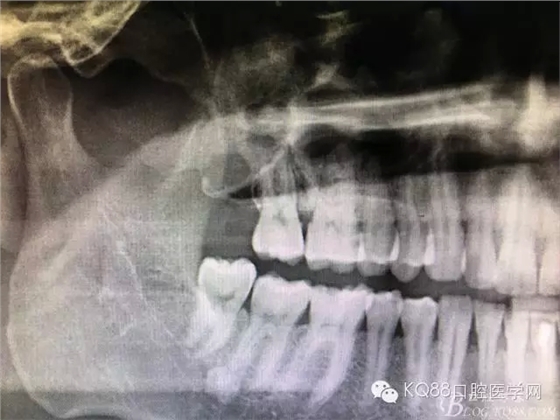

圖2.術(shù)前做全景片影像檢查:18頰舌向高位阻生,牙冠位于17牙根的正上方,懷疑18位于上頜竇內(nèi)。

圖18.術(shù)后的全景片影像檢查:

圖19.局部放大影像檢查:17牙根未見損傷